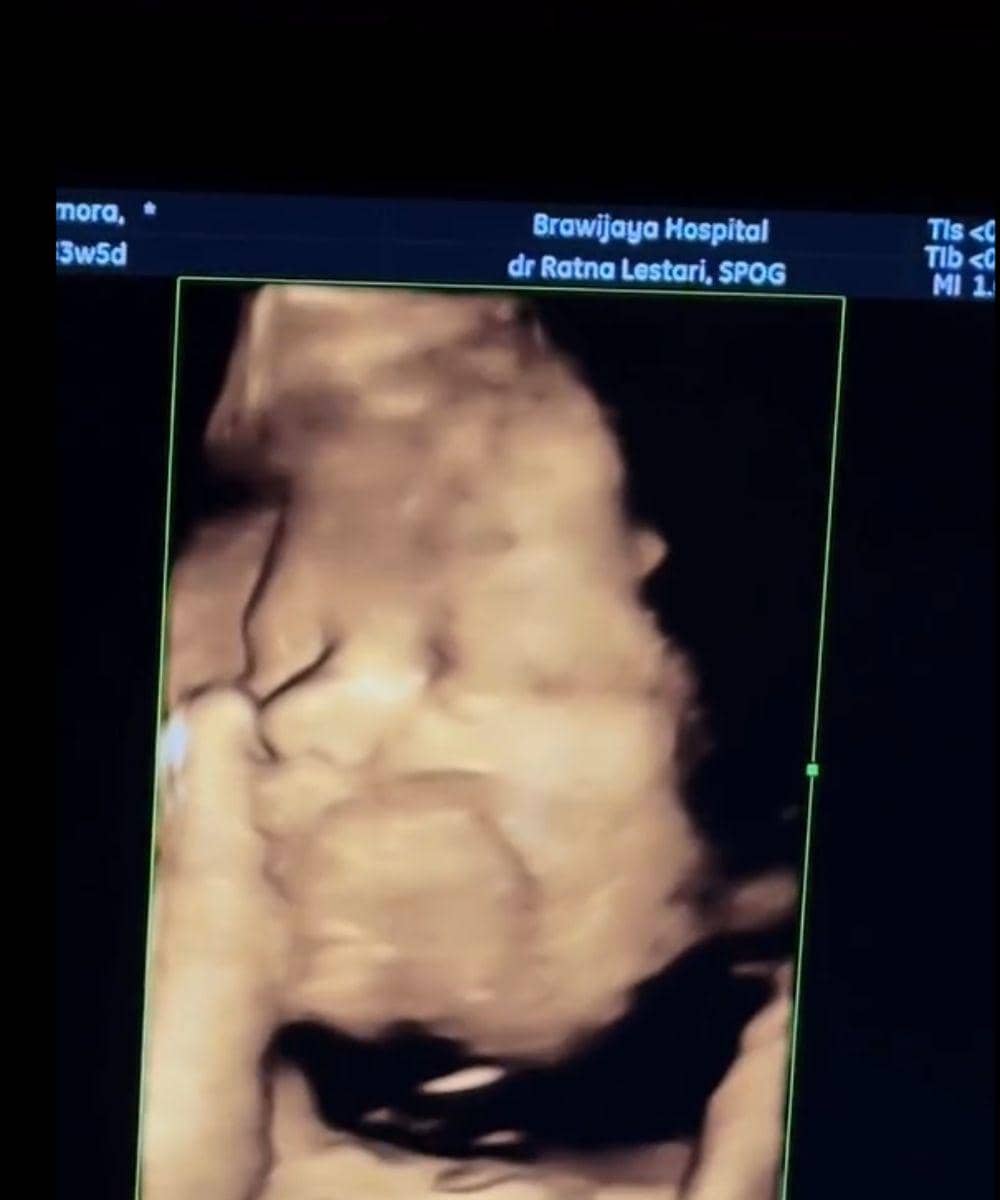

4. Potret calon anak pertama Steffi melalui hasil USG

Saat melakukan pemeriksaan USG, proses tersebut memperlihatkan visual janin dengan sangat jelas. Kehamilan Steffi yang memasuki trimester akhir membuat bentuk wajah bayi terlihat semakin sempurna, mulai dari hidung, pipi, hingga struktur wajah kecilnya yang menggemaskan.

Hal yang semakin menggemaskan adalah sang bayi tampak sedang mengisap jempol saat pemeriksaan berlangsung. Gerakan tersebut terlihat jelas di layar monitor. Selain itu, netizen juga banyak yang menyadari bahwa hidung sang putri sudah terlihat mancung.